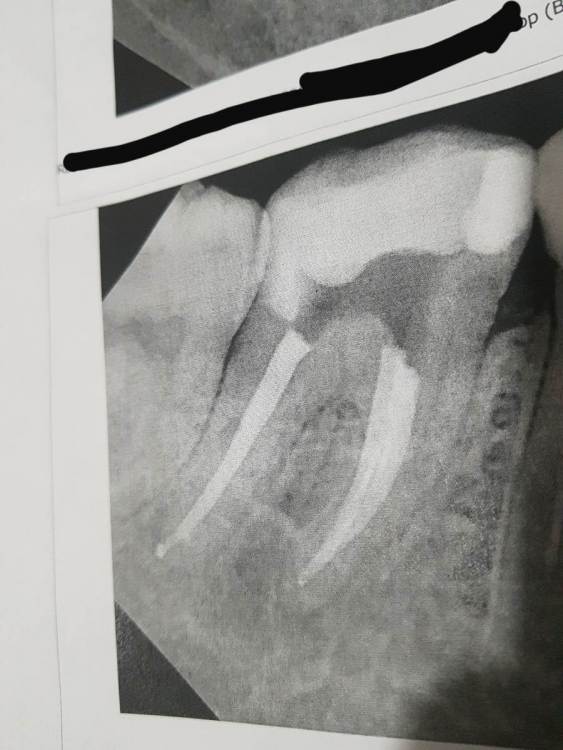

Анастасия577 Опубликовано 21 декабря, 2024 Поделиться Опубликовано 21 декабря, 2024 В 04.06.2022 в 10:32, Гарриевич сказал: Зависит от типа выведенного материала (силера). Рассасывается это от 15 до 100%, но в 100% не несёт в себе никакой опасности Скажите пожалуйста, а вот это уже слишком сильно вышло за пределы? Или это норма и тоже рассосётся со временем? Ссылка на комментарий

Бардо Опубликовано 21 декабря, 2024 Поделиться Опубликовано 21 декабря, 2024 2 часа назад, Анастасия577 сказал: Скажите пожалуйста, а вот это уже слишком сильно вышло за пределы? Или это норма и тоже рассосётся со временем? Не думаю, что это рассосется, но мы боремся не с пломбировочным материалом за зубом, а с инфекцией в зубе. В вашем зубе скорее всего есть еще корневые каналы, я бы посоветовал вам обратиться к доктору, который работает с увеличением и изоляцией. 1 Ссылка на комментарий

Анастасия577 Опубликовано 22 декабря, 2024 Поделиться Опубликовано 22 декабря, 2024 19 часов назад, Бардо сказал: Не думаю, что это рассосется, но мы боремся не с пломбировочным материалом за зубом, а с инфекцией в зубе. В вашем зубе скорее всего есть еще корневые каналы, я бы посоветовал вам обратиться к доктору, который работает с увеличением и изоляцией. Какой из них? Там два разных зуба. В нашей местности нет таких специалистов. Я перепроверила у другого врача, в другой клинике, в другом городе, он сказал что для наших городов это одна из лучших работ, в основном каналы чистят хуже. Ссылка на комментарий

Бардо Опубликовано 22 декабря, 2024 Поделиться Опубликовано 22 декабря, 2024 45 минут назад, Анастасия577 сказал: Какой из них? Там два разных зуба. В нашей местности нет таких специалистов. Я перепроверила у другого врача, в другой клинике, в другом городе, он сказал что для наших городов это одна из лучших работ, в основном каналы чистят хуже. Проблемы есть с обоими зубами, возможно имеет смысл съездить в ближайший более-менее крупный город, в наше время уже нет большой проблемы найти доктора, который может справиться с такими зубами. Вам как пациенту, повторюсь, стоит обращать внимание на наличие увеличения и изоляции. Ссылка на комментарий